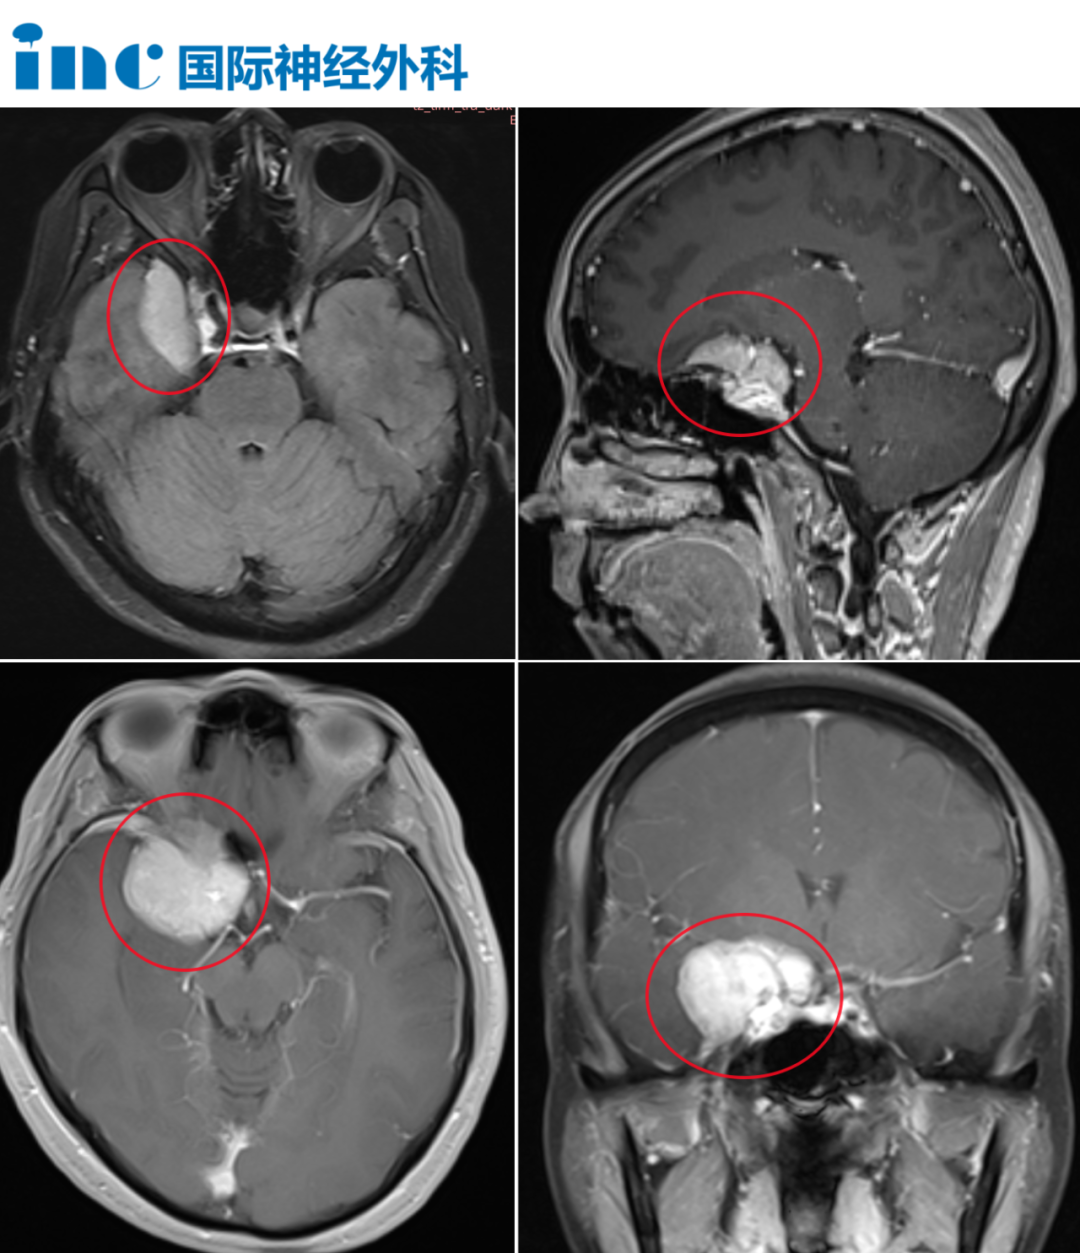

2021年3月,患者在就诊当天完成了MRI和CT检查。最初的影像报告提示为“纤维结构不良”。随后经住院进一步详细读片,诊断被更正为:多发脑膜瘤,主要位于左右额叶及顶叶区域,并伴有明显的邻近骨质增生,形成骨性隆起(见上图)。想要了解孕激素为何会引起脑膜瘤,点击阅读:INC国际神外大咖福教授:超25万女性队列研究——使用大剂量激素易诱发脑膜瘤风险!

带着种种疑问,她找到福教授。我们先来看看蒋女士的病灶究竟在哪——增强核磁共振提示:右侧跨前中颅窝紧贴颅骨见一围绕蝶骨眶面生长不规则占位性病变,约32mmx41mmx42mm;左侧额部大脑镰小结节影,约1.0cmx1.2cm;脑干桥臂见小结节异常信号影。